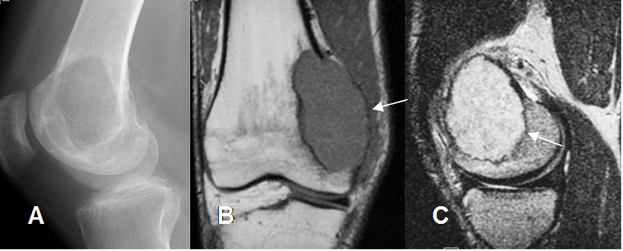

Fig 123. Tumor de células gigantes.

A: Rx lateral. Lesión expansiva y sin ruptura de la cortical, en la cabeza del peroné.

B: RM sagital y C: RM axial en T1 con contraste. Formación de seudocápsula y gran realce del contraste.